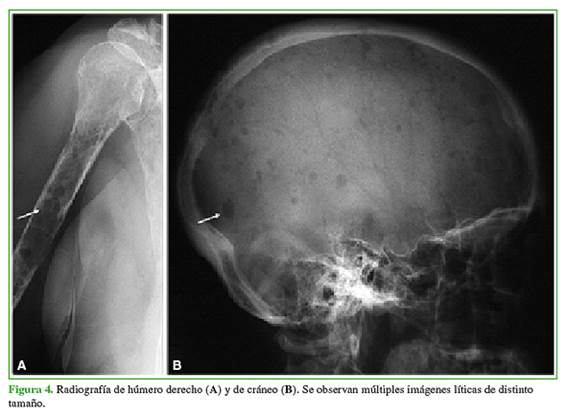

Se manifiesta con una amplia gama de anomalías radiográficas que pueden ser resumidas en cuatro patrones principales: 1) lesiones líticas múltiples bien definidas que afectan predominantemente al esqueleto axial, 2) osteopenia esquelética difusa, 3) plasmocitoma solitario, una única lesión grande más frecuente en un cuerpo vertebral o en la pelvis y 4) mieloma osteoesclerosante.

La distribución del MM se corresponde con la médula ósea roja en el individuo mayor, se observa el compromiso predominante del esqueleto axial y apendicular proximal: cuerpo vertebral (más frecuente), costilla, cráneo, cintura escapular, pelvis y huesos largos. En las imágenes, la gran mayoría de las lesiones del MM son puramente líticas, claramente definidas y con festoneado endóstico cuando se apoyan en la cortical ósea. No obstante, el 3% de los pacientes puede presentar lesiones escleróticas.

El MM diseminado tiene dos apariencias radiográficas comunes, aunque cabe señalar que inicialmente las radiografías pueden ser normales en pacientes sintomáticos. Los dos patrones principales son: numerosas lesiones óseas líticas bien delimitadas (más frecuente), como el cráneo con gotas de agua (Figura 4) o la osteopenia generalizada que suele asociarse con fracturas por compresión vertebral/vértebra plana.